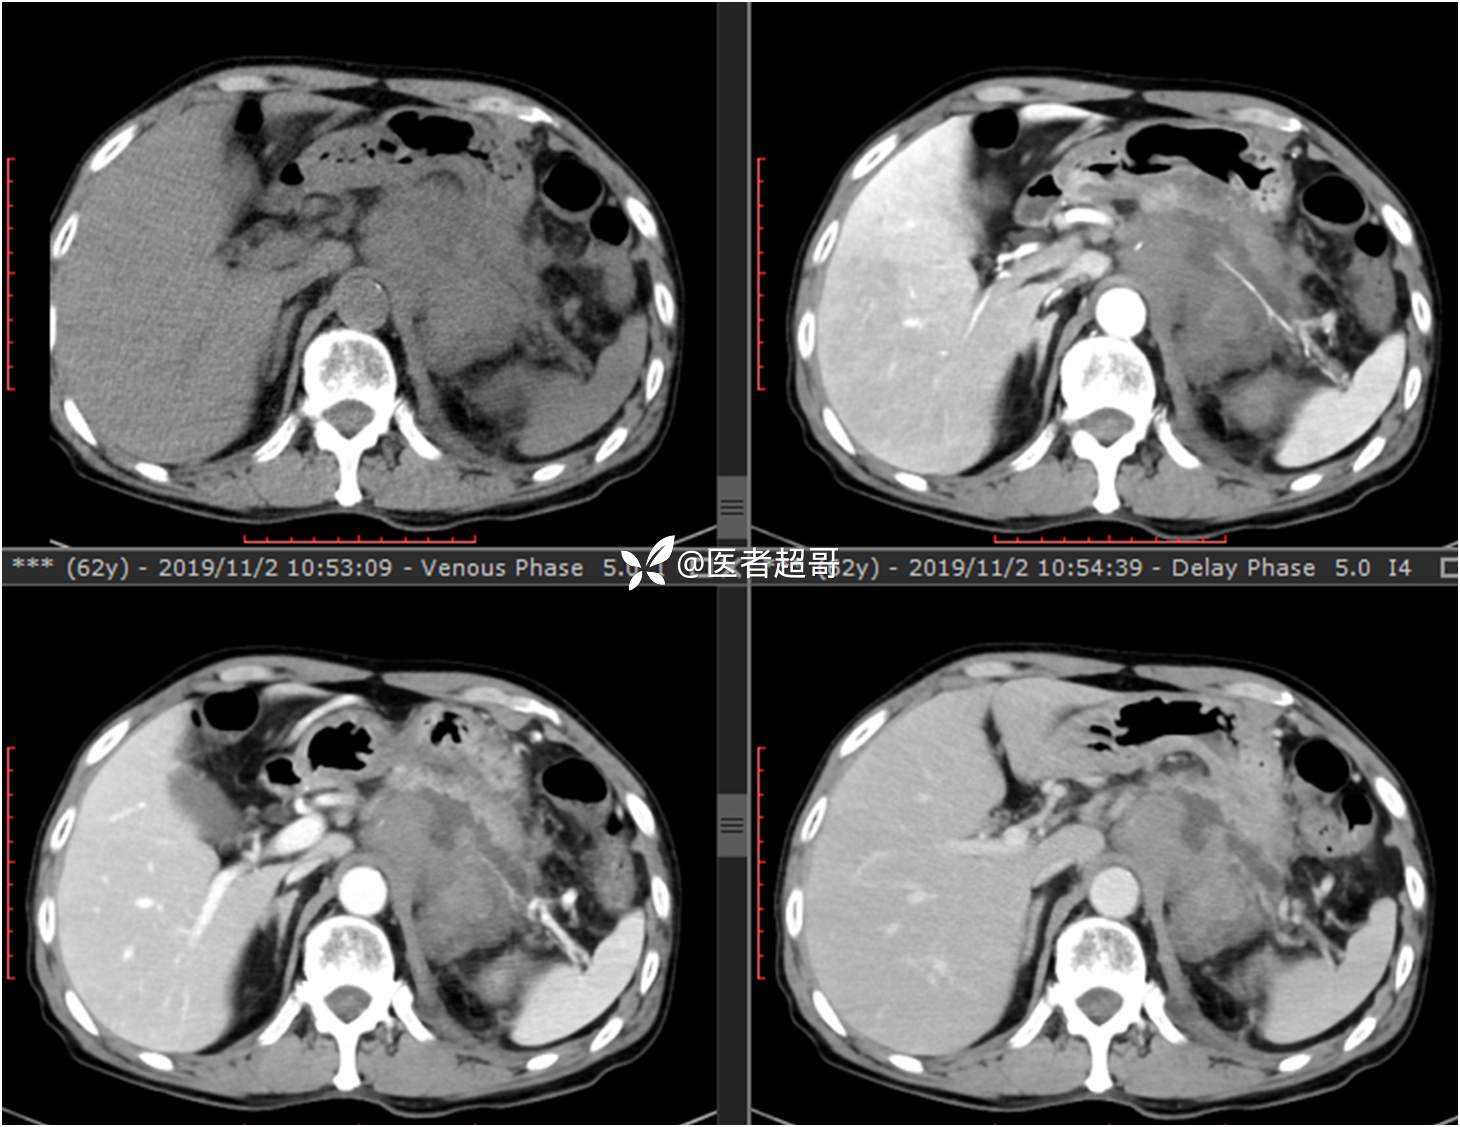

现病史:患者于1月前无明显原因及诱因出现左上腹部疼痛,为间断性疼痛,无恶心、呕吐,无寒战、高热,无腹胀、腹泻等伴随症状,在外未行特殊处理,患者于1周前自觉疼痛加重,为求诊治患者曾就诊于市东城医院,行全腹部强化CT提示:左肾上腺区肿块,符合恶性肿瘤侵犯左肾、胰腺及腹膜后大血管CT表现,行保守治疗,症状缓解,今患者为求进一步诊治,来我院就诊,行腹膜后占位穿刺活检病理提示:(腹膜后占位穿刺)小细胞背景内见细胞浆红染的神经节样细胞,建议到病理科加做免疫组化进一步明确诊断,遂以“腹膜后肿物”收入院,患者自发病以来,神志清,精神可,饮食、睡眠差,大小便正常,体重未见明显改变。